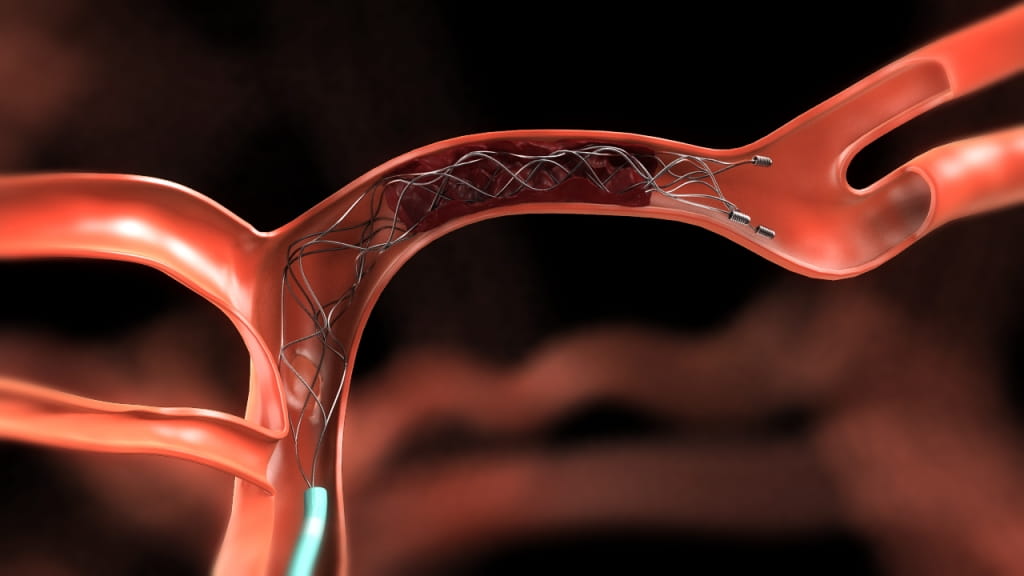

Solitaire_credit Covidien

Less sophisticated devices tested previously produced disappointing results in clinical trials. But the new studies tested more modern devices such as a retrievable stent, a tiny wire cage attached to a catheter that is threaded through an artery in the groin to the blocked artery in the brain. The stent opens and traps the clot, allowing doctors to extract the clot and reopen the artery nearly every time.

Image courtesy of Covidien